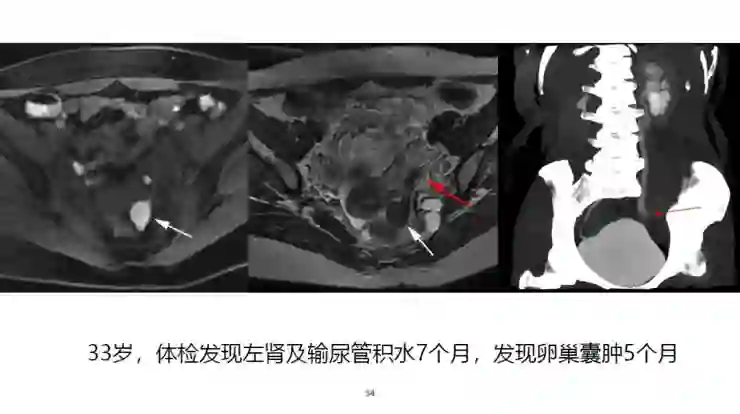

对于盆腔,目前医院里主流的影像学检查主要包括超声、CT和核磁,其中,最常见的是超声。虽然超声科的超声检查很方便也很常见,但是它给出的报告却因操作者而异,而且不够直观。相比之下,放射科的CT和磁共振图像就很直观,比如,CT会根据组织密度的不同来成像,骨头就是白的,像低密度的水、尿液和脂肪等就是黑的,但是CT对于盆腔软组织、比如子宫的密度都很接近,显示不清楚,而磁共振就很好地解决了这个问题,能够看清楚很多器官和组织,比如上图明亮的卵巢囊肿和分三层结构的子宫,这一特点决定了磁共振在盆腔检查里有很好的适用性。

上图就是一个横轴位图像,我们能看到骨头,能看到双侧卵巢,能看见卵泡,它是最常用的。中间的这个图像是矢状位,和之前看的解剖图一样,能看见子宫内膜、结合带、肌层和浆膜、宫颈,这张图是女性盆腔里大家最愿意看到的一张图。它最直观,如果患者长了肌瘤和畸形,都可以看得特别清楚。后面这个是冠状位,主要作为参考,这个图像上能看到卵巢相对位置等等一般观察女性盆腔,主要使用的是横轴位图像和矢状位图像。

所以放射科医生是怎么读片?就是一层一层地观察图像。举个例子,这是一个T2加权像序列,可以看到膀胱,尿液是亮的,然后能看到子宫,然后能看到双侧卵巢,接着是宫颈,宫颈再往下一层一层延续下去就是阴道。